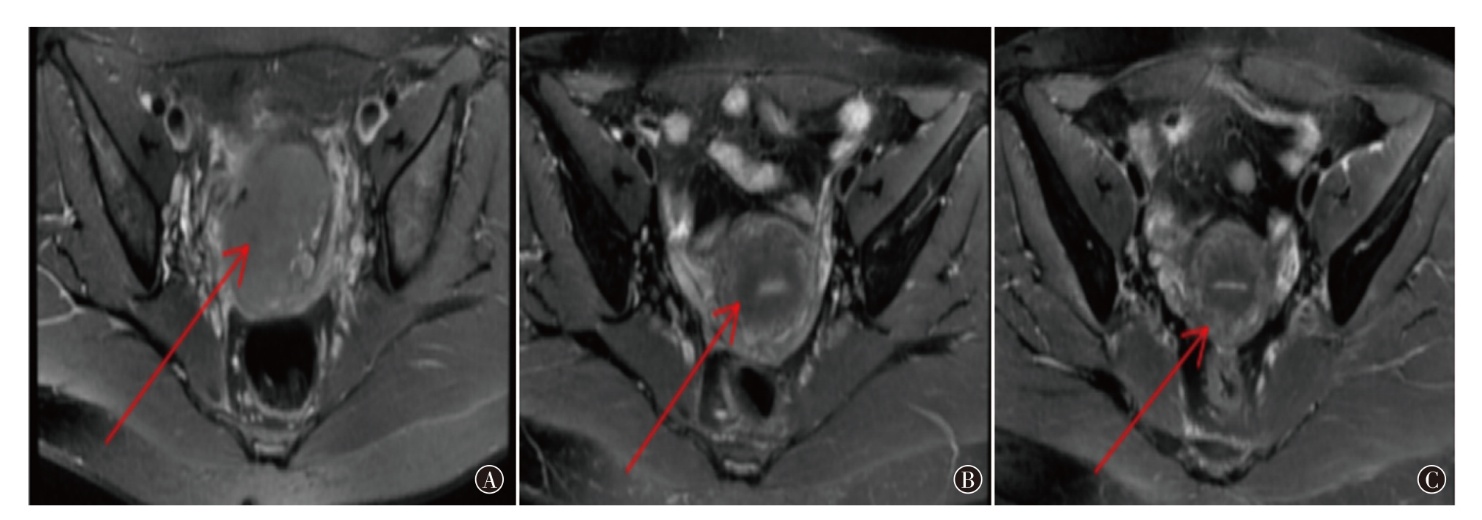

Objective To observe the efficacy and safety of anlotinib maintenance treatment in patients with locally advanced cervical cancer (LACC) after concurrent chemoradiotherapy. Methods From October 2021 to August 2022, 68 patients with LACC admitted to Qingdao Municipal Hospital were selected as the research subjects. According to different treatment regimens, they were divided into an observation group of 32 cases (receiving anlotinib maintenance treatment after concurrent chemoradiotherapy) and a control group of 36 cases (receiving concurrent chemoradiotherapy alone), with 21 days as one course of treatment. Serum tumor marker squamous cell carcinoma antigen (SCC) was reexamined after each course of treatment. Imaging MR was performed every 2 courses of treatment to evaluate the changes in the size of cervical lesions, and the occurrence of drug-related adverse reactions in the two groups of patients was observed. The progression-free survival (PFS) was compared between the two groups. Results By the end of follow-up,the SCC and maximum cervical lesion diameter in the observation group were (5.81±0.62) ng/ml and (3.66±0.84) cm, respectively, and those in the control group were (6.79±0.53) ng/ml and (4.32±0.68) cm, respectively, with statistically significant differences (t=8.50, P<0.001; t=4.32, P<0.001). The complete remission rate of the observation group was 81.25% (26/32), which was significantly higher than that of the control group (50.00%, 18/36), with a statistically significant difference (χ2=7.24, P=0.007). The incidence of secondary hypertension in the observation group was 46.88% (15/32), higher than 22.22% (8/36) in the control group, with a statistically significant difference (χ2=4.60, P=0.032), however, all were grade 1-2. There were no statistically significant differences in the incidence of hematological toxicity [62.50% (20/32) vs. 50.00% (18/36), χ2=1.07, P=0.300], gastrointestinal reactions [34.38% (11/32) vs. 25.00% (9/36), χ2=0.72, P=0.397], radiation cystitis [15.63% (5/32) vs. 11.11% (4/36), χ2=0.30, P=0.584], radiation proctitis [18.75% (6/32) vs. 11.11% (4/36), χ2=0.79, P=0.375] and proteinuria [21.88% (7/32) vs. 19.44% (7/36), χ2=0.06, P=0.805] between the observation group and the control group. The median PFS in the observation group was 23.75 months, which was significantly longer than 15.16 months of the control group, with a statistically significant difference (χ2=4.28, P=0.034). Conclusions The complete remission rate of concurrent chemoradiotherapy followed by anlotinib maintenance treatment for LACC is higher than that of concurrent chemoradiotherapy alone, the adverse reactions are controllable, and can prolong the PFS of patients.